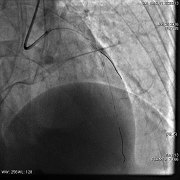

急诊PCI

患者经济原因,仅于前降支中段植入一枚2.5*36mm乐普支架

非罪犯血管病变未处理